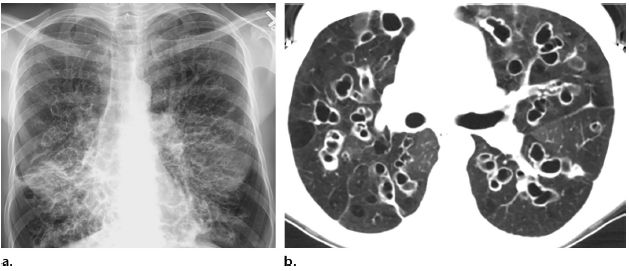

支氣管擴張的診斷主要依據患者的病史、癥狀和體征,以及輔助檢查如高分辨率CT掃描等,醫(yī)生會根據患者的具體情況進行綜合分析,以確定診斷。